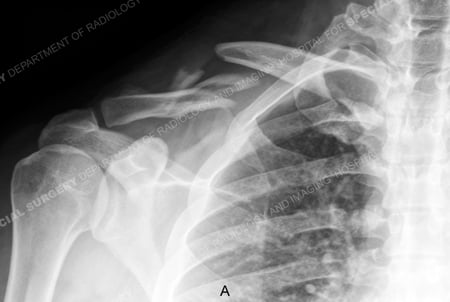

Anteroposterior x-ray revealing a right-sided displaced mid-shaft clavicle fracture.